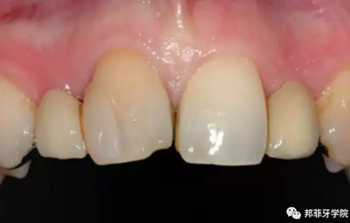

26歲女性患者,雙側(cè)上頜側(cè)切牙先天缺失,對原有修復(fù)體的“形態(tài)”、“光澤”等方面不滿意,希望重新修復(fù)(圖1&2)。12及22原為粘接橋修復(fù),11根管治療史;拆除原修復(fù)體后余鄰牙完整,未見病理性探診深度。無系統(tǒng)疾病史。患者期望值較高,告知治療流程佩戴臨時卡環(huán)義齒等(圖3)、費用、風(fēng)險后表示接受治療。

圖1:治療前口內(nèi)情況